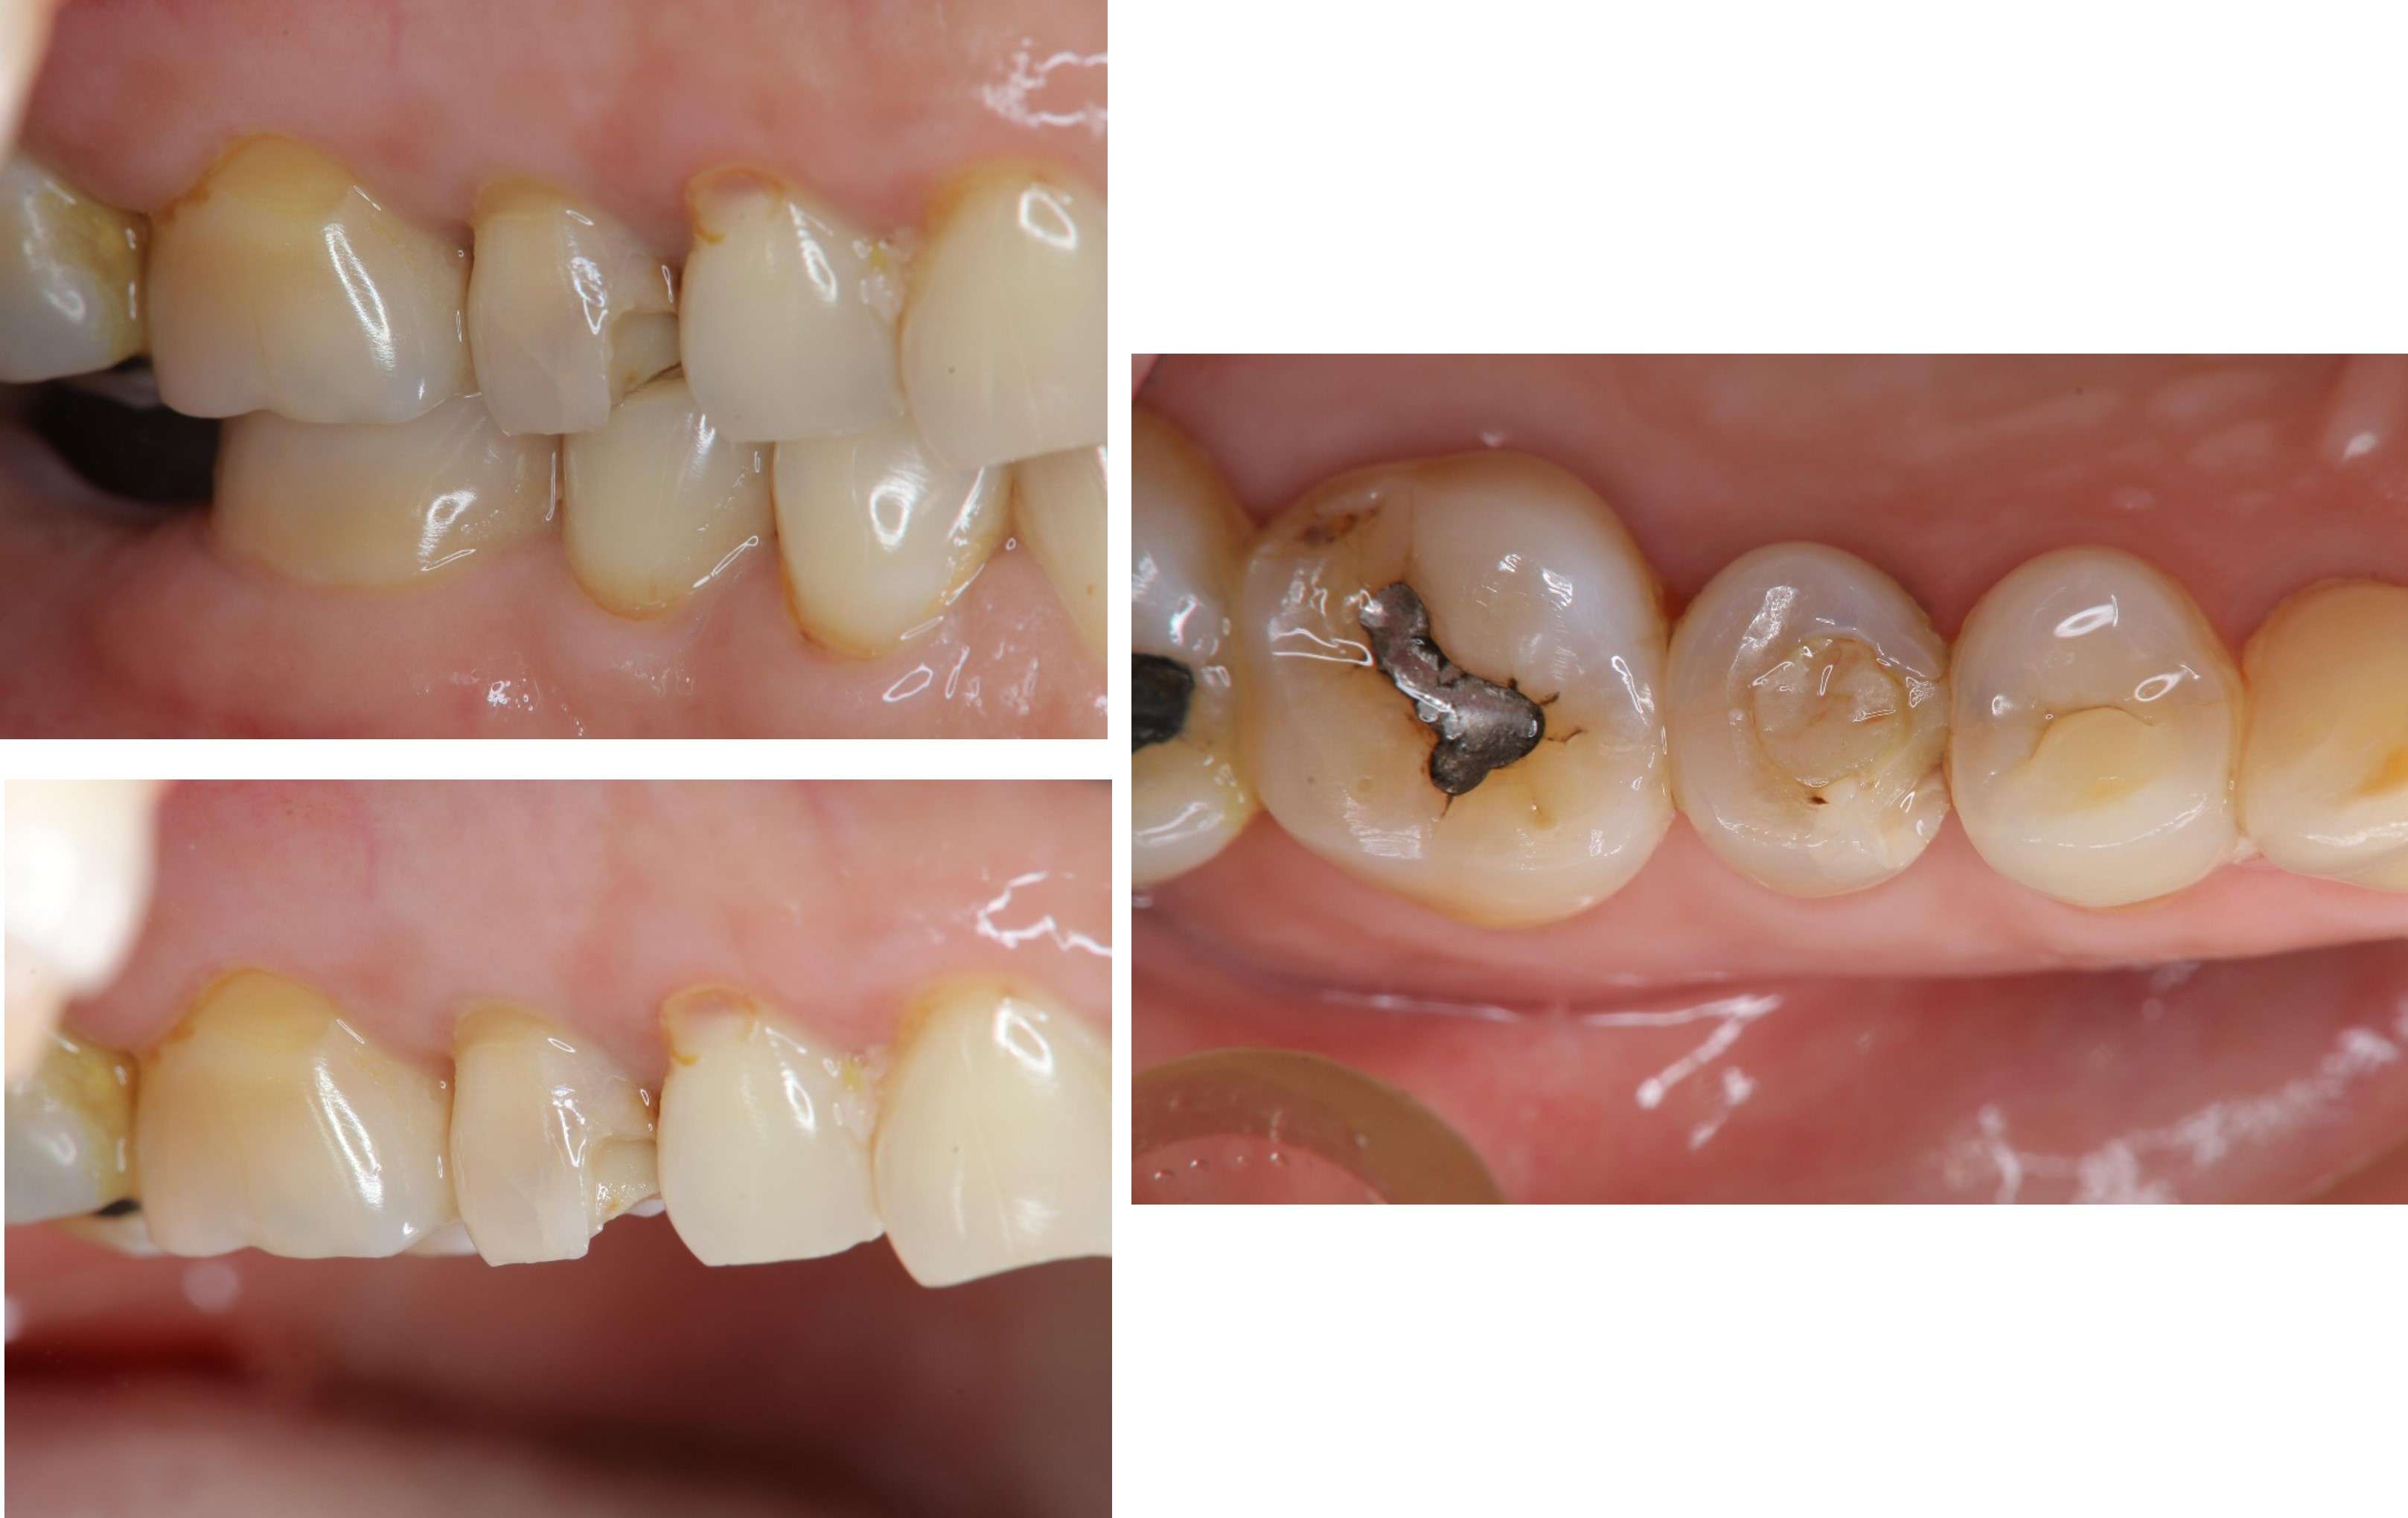

治療前,嚴重二次蛀牙

根管治療後再次牙裂